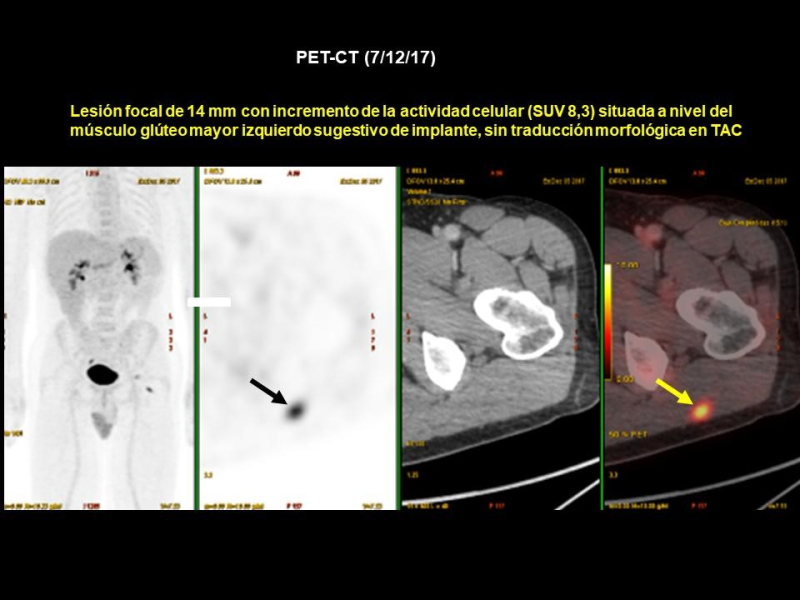

Se realiza PET-CT (7/12/17) previo a resección de adenopatía inguinal izquierda (Figs. 3 y 4), hallándose lesión focal de 14 mm con incremento de actividad metabólica (SUV 8,3) situada a nivel del músculo glúteo mayor izquierdo sugestivo de implante secundario, sin traducción morfológica en CT. Además, adenopatía inguinal izquierda con incremento de la actividad metabólica (17mm/SUV 4) compatible con posibles cambios inflamatorios secundarios a punción reciente. Una nueva ecografía muestra lesión nodular en el espesor del músculo glúteo mayor, en relación con depósito secundario, de fácil acceso y susceptible de marcaje por ROLL (Fig. 5). También se encuentran dos adenopatías inguinales izquierdas, con criterios de posible secundarismo ganglionar.